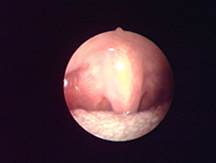

適于精確損毀破壞內(nèi)部組織。